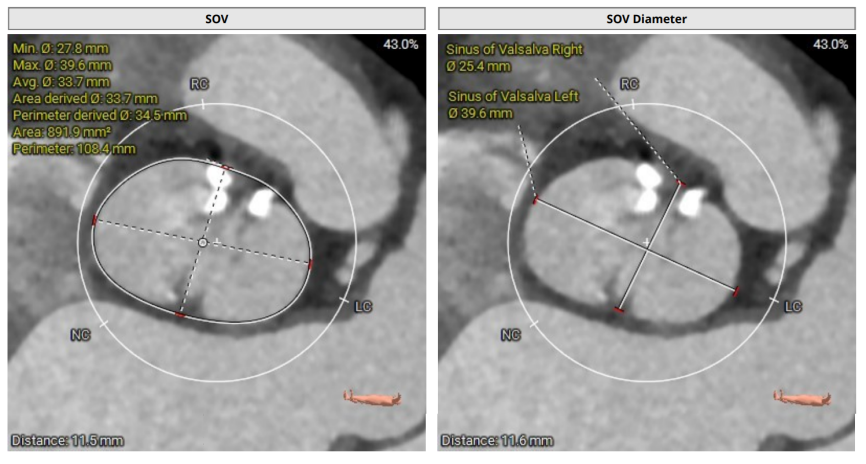

术前CT

术前CT(上下滑动查看更多图片)